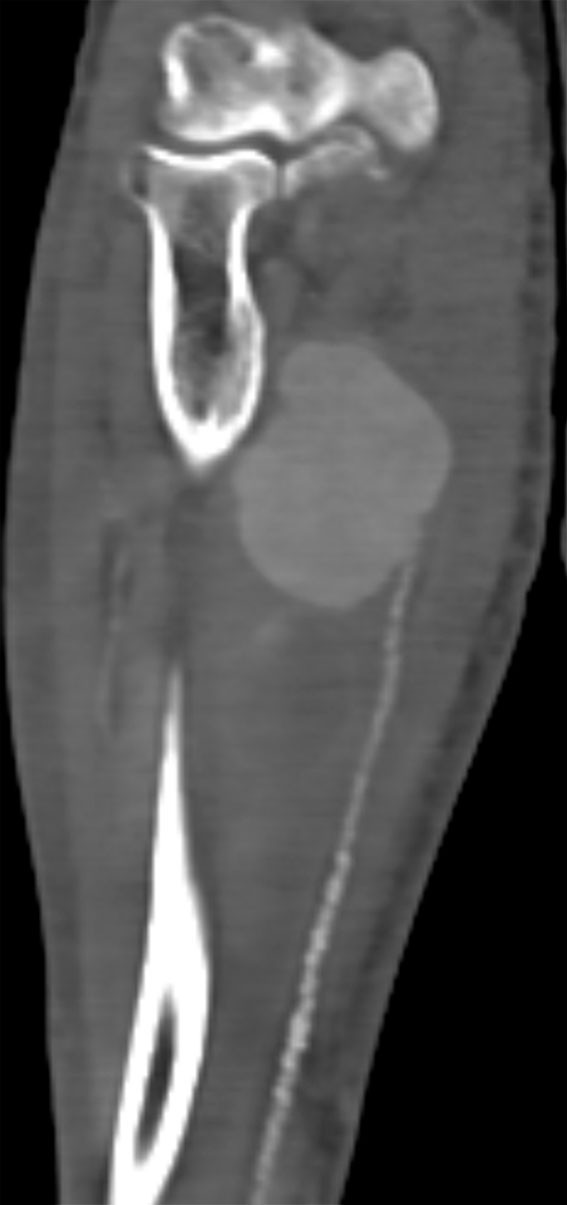

Twelve days after admission, the patient noticed a painful swelling in his right forearm. Ultrasound revealed an aneurysm on the ulnar artery. CT angiography taken the same day confirmed the ultrasound findings and revealed an aneurysm measuring 7.5 × 4 cm (Figure 1). There were numerous atherosclerotic changes distal to the aneurysm. Clinical examination found good circulation to the hand on occlusion of the ulnar artery.